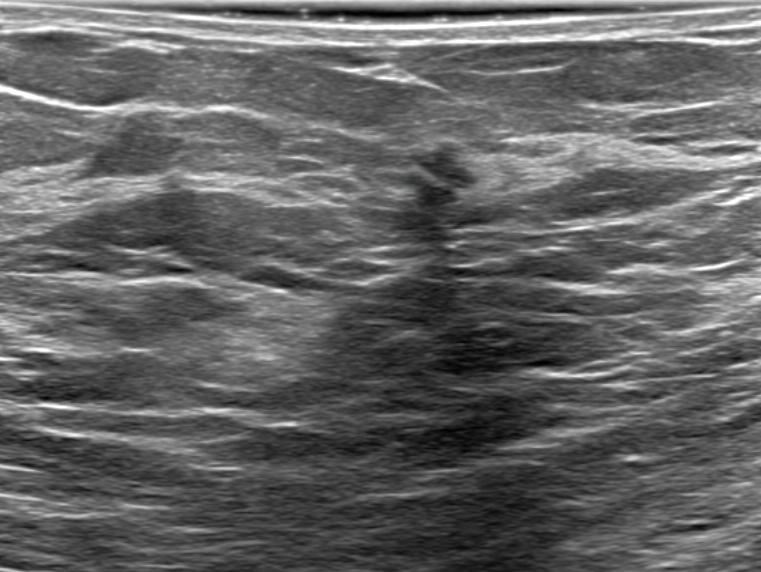

Merged Breast Dataset (MBD) The developed strategies are validated on four public breast lesion datasets, including BUSI[28], DatasetB[29], BrEaST[30], and BUS-BRA[31]. Among the datasets considered, BUS-BRA stands out for its substantial size, contributing over 1,800 images on its own. Given that all images across these datasets are meticulously annotated with pixel-level delineations, we then merged them into an enhanced dataset comprising approximately 3,000 images. We name the merged breast dataset as MBD for simplicity. We then randomly partition them into the train set, validation set, and test set in a ratio of 7:1:2. The detailed composition can be seen in Table I.

KVASIR-SEG KVASIR-SEG is an endoscopic dataset specifically created for pixel-level segmentation of colonic polyps[34], and it was featured as part of the MediaEval 2020 benchmarking challenge. The dataset includes 1,000 gastrointestinal polyp images, each paired with corresponding segmentation masks. These masks were carefully annotated and validated by board-certified gastroenterologists to ensure high diagnostic accuracy [34]. In this study, we randomly divided the dataset into 700 images for the training set, 100 images for the validation set, and 200 images for the testing set, along with their respective labels. For datasets containing validation datasets, we only validate the performance of the model during training after each epoch and iteratively save the weights that give the best performance on the validation set. When model training finishes, we reload the weights from the best-performing model for testing on the unseen test set. Otherwise, the testing set is used as the validation set instead. Some examples and corresponding labels can be seen in Figure 6.